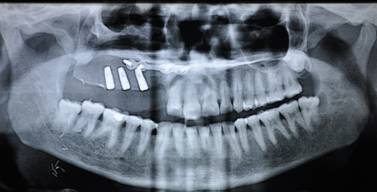

OPG SHOWS RECONSTRUCTION OF MAXILLA WITH OSTEOMYOCUTANEOUS ILLIAC BONE GRAFT AND IMPLANTS